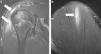

En el último tiempo, se han reportado en boxeadores roturas parciales del deltoides, ubicadas a nivel del vientre muscular y la unión miotendinosa adyacente a su inserción humeral, donde habitualmente se encuentran en asociación con edema óseo (fig. 10). El tratamiento suele ser con reposo, excepto en el desgarro grado III con avulsión en la inserción humeral que se realiza una reparación quirúrgica8.

Desgarro del músculo deltoides. Las secuencias ponderadas en STIR, planos (a) coronal y (b) sagital, visualizan un desgarro del vientre muscular a nivel proximal y medio con compromiso de la unión miotendinosa en su inserción humeral, donde convergen los 3 grupos de fibras (clavicular, acromial y escapular) (flechas). El paciente practicaba boxeo.

La lesión del coracobraquial suele estar asociada a roturas de otros músculos del brazo de afección más frecuente (como el bíceps o tríceps), y el desgarro habitualmente se encuentra a nivel de la unión miotendinosa proximal, donde se vincula en general con una marcada cantidad de líquido y edema de partes blandas en forma subyacente (fig. 11). Puede producirse por origen traumático o por sobreuso en el caso de deportes como natación, tenis, golf, levantamiento de pesas o lanzamiento.